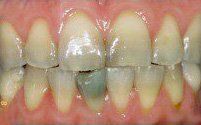

Smile Restoration Procedure

Patient needed multiple restorations, decay removed from upper teeth, crowns placed from canine to canine. Patient Missing 1st lower molar, implant and crown placed, chewing function restored. 2nd molar cracked, causing severe pain, nerve removed from tooth with root canal therapy